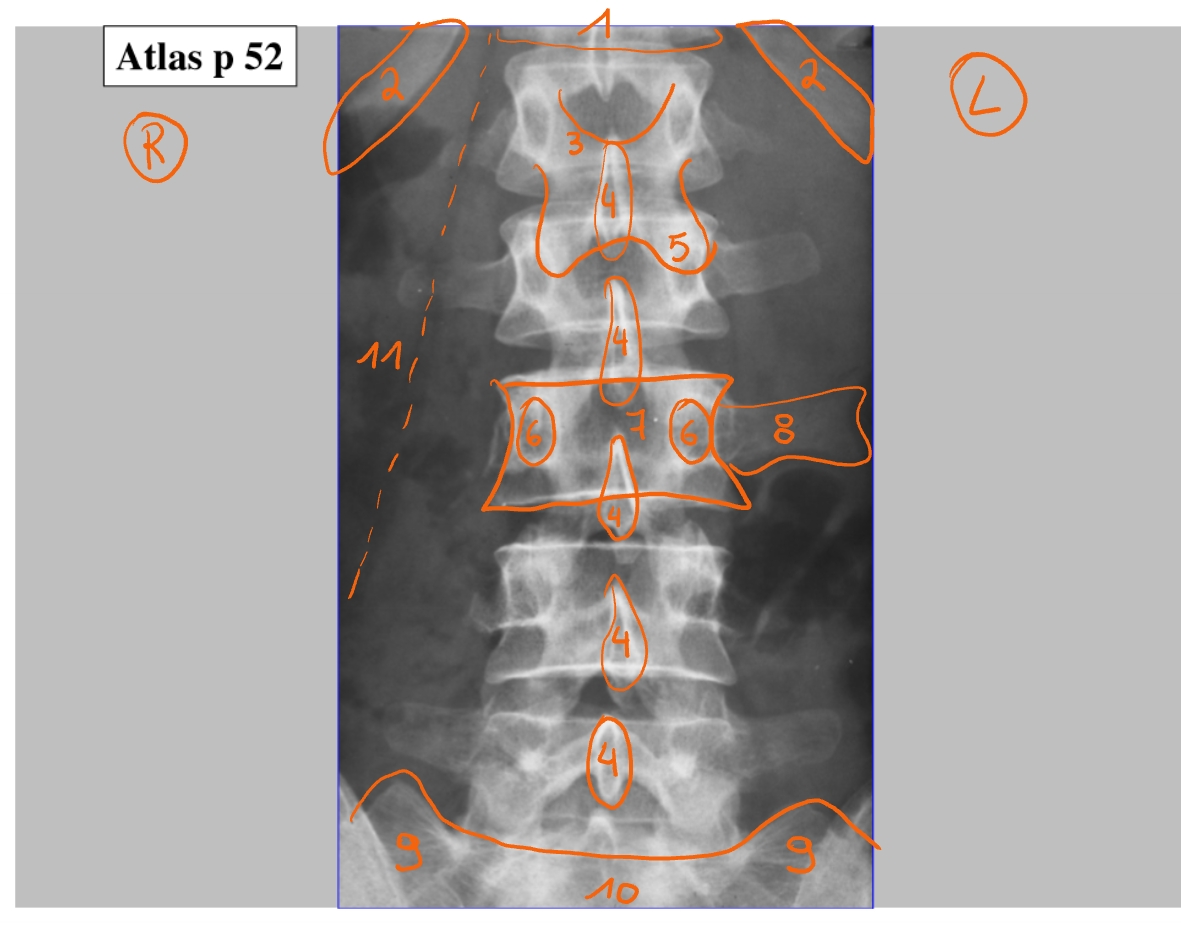

corpus T12

rib 12

zwevende rib

bovenrand van de arcus

processus spinosus

processus articularis inferior

pedikel

corpus L3

processus transversus (links)

ala van het sacrum (= de vleugels)

corpus S1

vetlijntje op de psoas-spier

rib 12

ribben niet perfect op elkaar want patiënt is een beetje gedraaid

corpus L3

pedikel

processus articularis superior

processus articularis inferior

processus spinosus

discus intervertebralis

spinale zenuw L2

foramen intervertebrale

sacrum